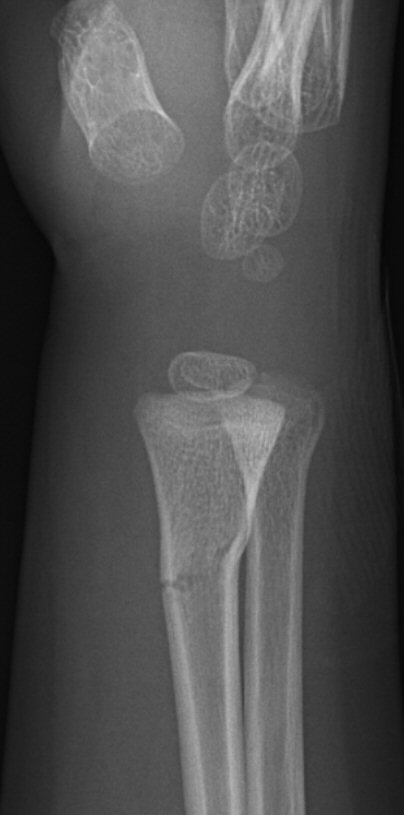

Dorsalbockad distal radiusfyseolys Salter-Harris typ 2 före och efter reposition

Dorsalbockad distal radius- och/eller ulnafyseolys (SH2)

Behandla icke-kirurgiskt om: [1]

- < 10 år för flickor, < 12 år för pojkar:

- ≤ 30° vinkelfelställning jämfört med anatomiskt läge

och

- ≤ 1/2 benbredds ad latus

- ≥ 10 år för flickor, ≥ 12 år för pojkar:

- ≤ 20° vinkelfelställning jämfört med anatomiskt läge

- ≤ 1/4 benbredds ad latus dorsalt

Icke-kirurgisk behandling:

- Semicirkulärt gips på underarmen (hög gipsskena hos små barn, det ramlar annars av), alltså bredare gips som ger trepunktstöd. Dorsalt vid dorsalbockning, volart med handleden dorsalextenderad vid volarbockning.

- Återbesök med röntgenkontroll efter 5-7 dagar [1], förutom vid odislocerad fraktur, då behövs inget återbesök.

- Vid försämrat läge men inom gränsvärde vid återbesöket: ny röntgenundersökning efter ytterligare 5 dagar. [1]

- Avgipsning i hemmet 3-4 veckor efter skadan. [1]

- Undvik risker 2 veckor efter avgipsning. [1]